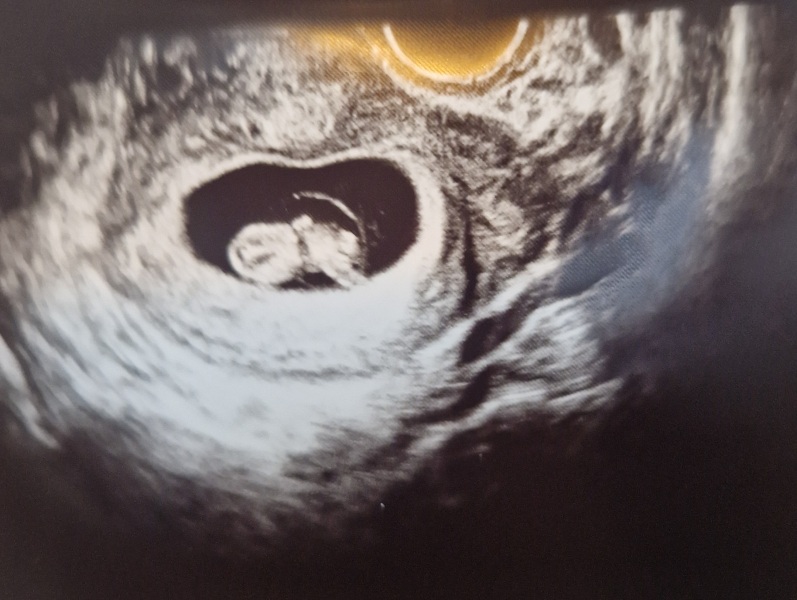

Just wanted to share a positive update. I spent the last several days terrified because my symptoms had gone, which happened in my last pregnancy that didn't stick. I'm still abroad but decided to get checked out instead of waiting. Was so relieved to see a wiggly baby on the screen with a strong heartbeat. Measuring ahead of what I thought, so I'm 9 weeks today with a revised due date of 4 September. Feeling so happy and much calmer.

@WolfMother326 what an incredible scan picture! So happy & relieved for you 🥰